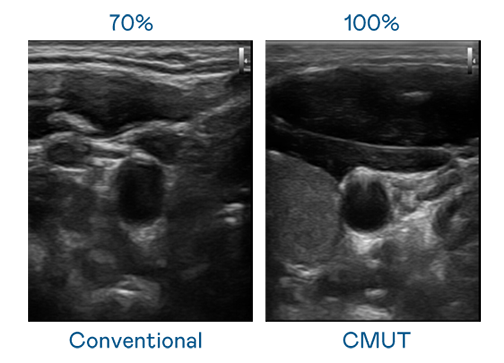

LEYU官網(wǎng)運用 TFT 陣列 (Array) 制程延伸尖端感測技術(shù),開發(fā)出多種感測元件的LEYU官網(wǎng)。高解析度、品質(zhì)穩(wěn)定且可量產(chǎn)的 CMUT 元件,可制作高解析度超音波探頭、貼片型探頭,對病患實施精準檢測與長時間生理監(jiān)測。